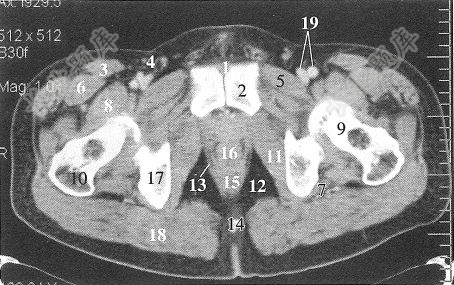

经耻骨联合下份层面,图中标16处的解剖结构是()

A、耻骨肌

B、前列腺

C、坐骨神经

D、股神经

E、精索静脉